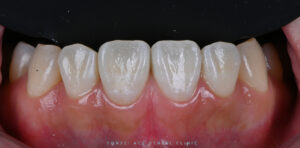

이렇게 아이콘 레진을 통해

앞니에 도드라져 보이던

흰 반점의 대비가 완화되었고,

주변 치아와의 색 차이도

한층 자연스럽게 정리되었습니다.

치아를 삭제하지 않은 채

탈회 부위 내부를 보완하는 방식으로 진행되었기 때문에

부담을 줄이면서 심미적인 개선을 기대할 수 있었으며,

환자분께서도 거울을 보실 때

이질감이 줄어들었다며 만족해 주셨습니다.